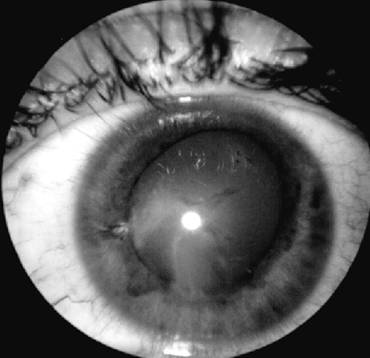

Corp strain intraocular

(pe traiect se observa plaga corneeana, gaura in iris,

cataracta localizata pe traiectul cristalinian)

Imaginea ecografica a corpului strain

(localizat in polul posterior al globului, la 3 mm de retina)

Uneori diagnosticul de corp strain intraocular este facilitat de evidentierea portii de intrare, sub forma unor leziuni corneene penetrante vizibile biomicroscopic, adiacente unor leziuni iriene -gauri in iris si cataracta localizata, care traseaza traiectul corpului strain in interiorul ochiului. Daca examenul fundului de ochi poate fi efectuat, acesta poate sa puna in evidenta corpul strain la nivelul vitrosului sau retinei (vezi plansa).

- examinarea ecografica realizata in ecografie tip A sau B, determina o localizare de precizie a corpului strain daca acesta are dimensiuni mai mari de 0,75mm (vezi plansa)